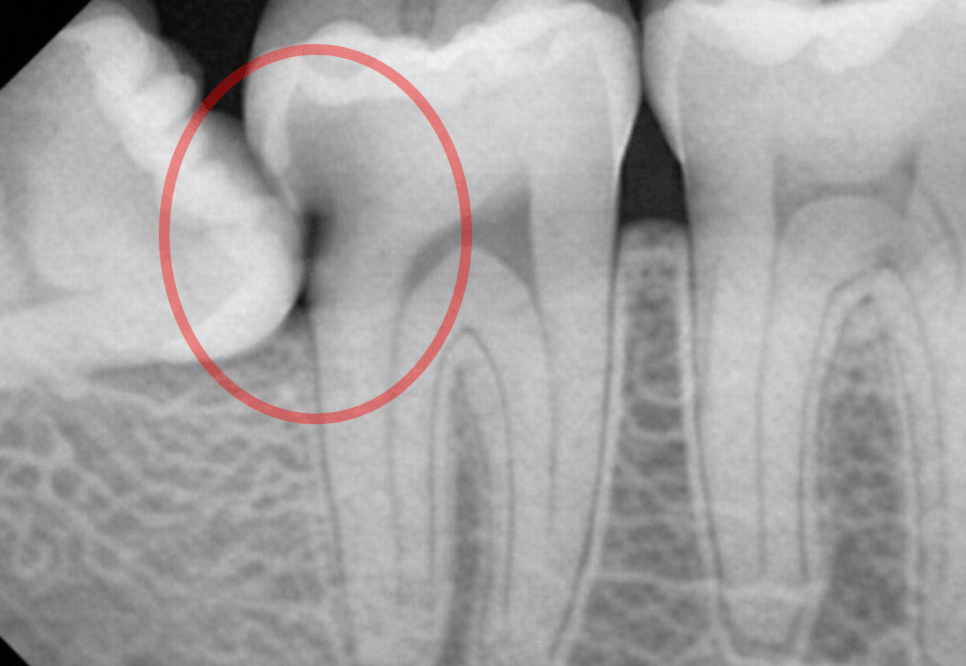

치배 형성 단계에서부터 비정상적인 각도로 발육해

구강 내로 수직으로 맹출하지 못하고

제2대구치의 원심면을 향해

수평으로 누워 있는 상태를 말합니다.

이는 제2대구치의 원심면 사이에 좁고 깊은

V자 형태의 틈새를 형성하며

이곳은 칫솔질이나 치실 사용만으로는

관리가 어렵기 때문에

음식 찌꺼기와 세균이 저류되면서

뮤탄스균의 완벽한 배양기 역할을 하며

바이오필름과 단단한 치석을 만들게 됩니다.

또한 사랑니 주변으로 치관주위염이 발생해

만성 염증을 일으켜 통증 및 출혈이 날 수 있으며

제2대구치의 뿌리나 치관을 지속적으로 압박해

주변 뼈의 밀도를 변화시키게 되어

골소실의 직접적인 원인이 됩니다.